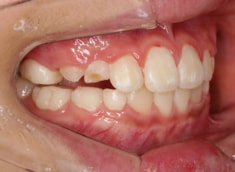

日本人の典型的なパターンである、上顎劣成長が顕著で、下顎骨体自体も大きい値を示しています。

鼻閉、LowTongue(低位舌)あり。

Facial Axis(顔の成長方向):95.8°なので、今後下顎前突傾向は旺盛であると予測されます。

上下顎の幅径と大臼歯の傾斜のギャップは平均値を越えて大きくなっており、上顎劣成長が顕著です。